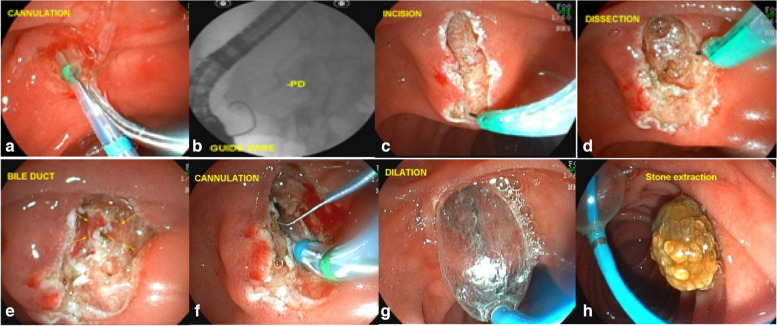

Subsequently, sectioning of the muscle fibers and of the common bile duct mucosa was performed, with bile outflow in most cases. Once the common bile duct mucosa was identified, the guide wire was introduced, confirmed by radioscopy and bile duct contrast (Fig. 3) (video 1).

If necessary, we can perform dilation with a 12- or 15-mm balloon catheter to facilitate removal of larger stones (Fig. 4).

However, in 63 cases (EFP failure), the guidewire was not passed into the common bile duct, most of the time due to minor bleeding or edema and loss of identification of structures in the dissection area. These cases were considered failure of the EFP in the first attempt. Of these 63 patients, 33 returned for a second attempt and what we found was a biliary fistula, with an easily identified orifice allowing the passage of the guide wire and the sphincterotome. However, in 30 cases, the patients did not return for the second attempt for various reasons. The reasons for non return were, worsening of the biliary obstruction or the clinical condition of the patient, complications of the underlying disease, the decision of the surgeon who conducted the case, and the indication of other alternatives for biliary drainage. As a result, 30 EFP patients did not return for the second attempt. Most of these cases were advanced cancer of the head of the pancreas that did not allow the guide wire to pass through the tumor. Such patients were referred for endoscopic ultrasound-guided biliary drainage, percutaneous transhepatic drainage or surgery.

This reinforces the idea that suprapapillary dissection is safer than countless unsuccessful attempts at cannulation through the ostium. The occurrence of acute post-ERCP pancreatitis is more dangerous than the sporadic occurrence of mild bleeding from papillary dissection, which is generally easily controlled. Another important point of the EFP procedure is that the wide exposure of the structures of the papilla leads to the formation of a fistula that, in most cases, is easily visualized by staining the bile around the fistular orifice, facilitating the cannulation of the bile duct (Fig. 6).